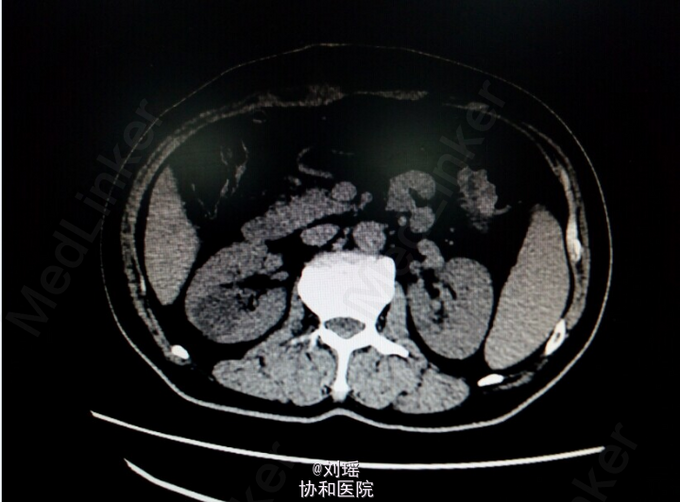

查体:生命体征平稳,慢性病容,皮肤巩膜重度黄染,右上腹T管,余无特殊。 辅助检查: 肝胆脾CT:右肾囊肿;胆总管粘液腺癌术后 T管造影:胆总管全段可见不同程度,不同大小之充盈缺损并不同程度狭窄,考虑为占位性病变。肝内胆管明显扩张。